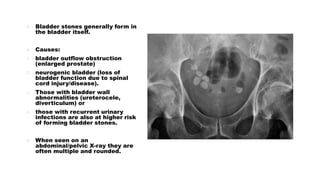

๏ต Bladder stones generally form in

the bladder itself.

๏ต Causes:

1. bladder outflow obstruction

(enlarged prostate)

2. neurogenic bladder (loss of

bladder function due to spinal

cord injury/disease).

3. Those with bladder wall

abnormalities (ureterocele,

diverticulum) or

4. those with recurrent urinary

infections are also at higher risk

of forming bladder stones.

๏ต When seen on an

abdominal/pelvic X-ray they are

often multiple and rounded.

๏ต Bladder stonesgenerally form in the bladder itself. ๏ต Causes: 1. bladder outflow obstruction (enlarged prostate) 2. neurogenic bladder (loss of bladder function due to spinal cord injury/disease). 3. Those with bladder wall abnormalities (ureterocele, diverticulum) or 4. those with recurrent urinary infections are also at higher risk of forming bladder stones. ๏ต When seen on an abdominal/pelvic X-ray they are often multiple and rounded.